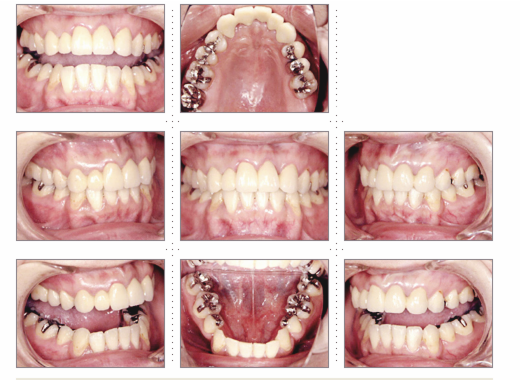

症例2

主婦 33才 女性

上下顎とも乳歯が残っており歯と歯の隙間が気になり、歯並びを奇麗にしたいとのご希望でした。

術後、家族や友人からもキレイになったと言われ、ご本人もご自分の歯のように気に入っていただけました。原因不明な頭痛もなくなり、快適な生活を送っていらっしゃいます。